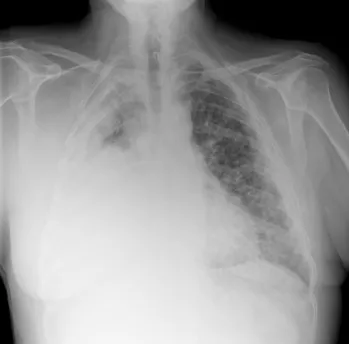

Plural Mesothelioma

Plural mesothelioma affects the lining around the lungs known as the pleural sac. This is the most common form of mesothelioma. The pleural sac is made up of a thin membrane commonly referred to as the mesothelium. It should be noted that the mesothelium secretes fluids that allow the lungs to expand and contract as part of the normal breathing process. Inhalation of asbestos fibers causes those fibers to stick to the pleural cavity, making it difficult to breathe.